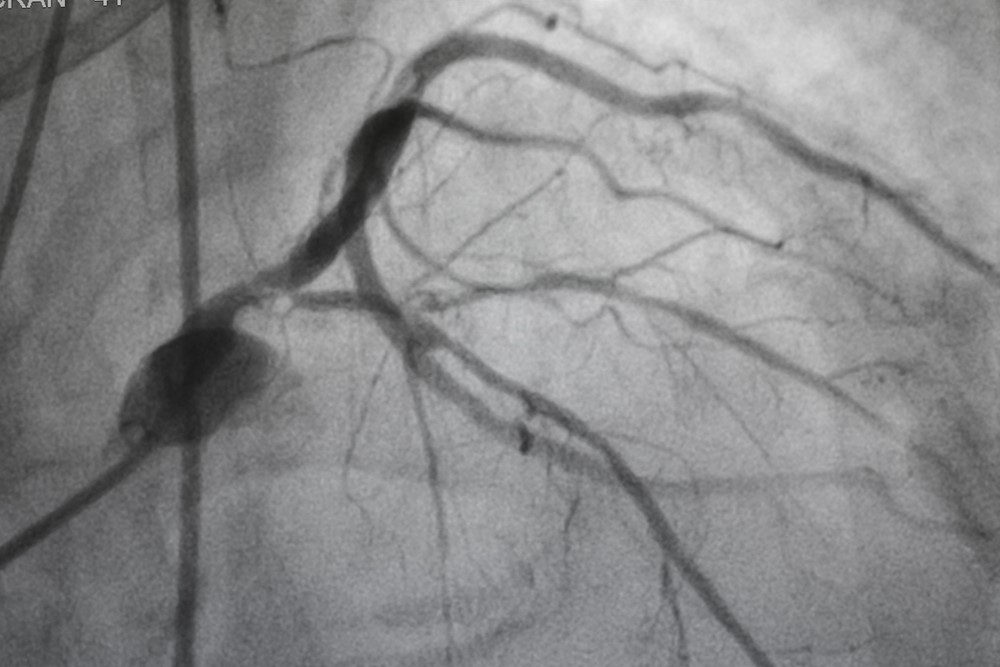

Mahfud : Saat itu pagi hari dan saya beristirahat. Di siang harinya, saya mengalami nyeri yang sama dan merasa gelisah, serta merasakan ada yang tidak tepat pada dada saya. Akhirnya saya meminta Paman saya mendampingi untuk melakukan pengecekan ke salah satu rumah sakit di pusat kota Semarang. Saat itu juga, saya bertemu dengan dokter jantung. Dan hal pertama adalah saya menyadari bahwa tekanan darah saya cukup tinggi di atas 155! Dokter lalu meminta saya mengecek kadar kolesterol saya lewat test darah. Hasil lab menyimpulkan kadar LDL saya sudah cukup tinggi di angka 170mg/dL. Dari situ, dokter mendiagnosa adanya penyumbatan awal pada pembuluh darah jantung saya, merujuk dari hasil darah dan keluhan yang saya rasakan. Selanjutnya dokter menyarankan saya melakukan test angiography untuk mengecek ada/tidaknya sumbatan pada pembuluh darah jantung saya. Namun karena saat itu disarankan menginap, saya memilih untuk pulang dahulu dan berniat melanjutkan pengecekan di keesokan hari.